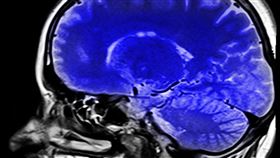

「空汙=腦毒」害失智!醫揭「做4事」護腦

空氣汙染不只造成肺癌,甚至加速大腦退化。胸腔暨重症專...

獨/空污世代下 醫:人類有了這些變化!

早在COVID-19疫情前就有不少民眾出門時習慣戴上...